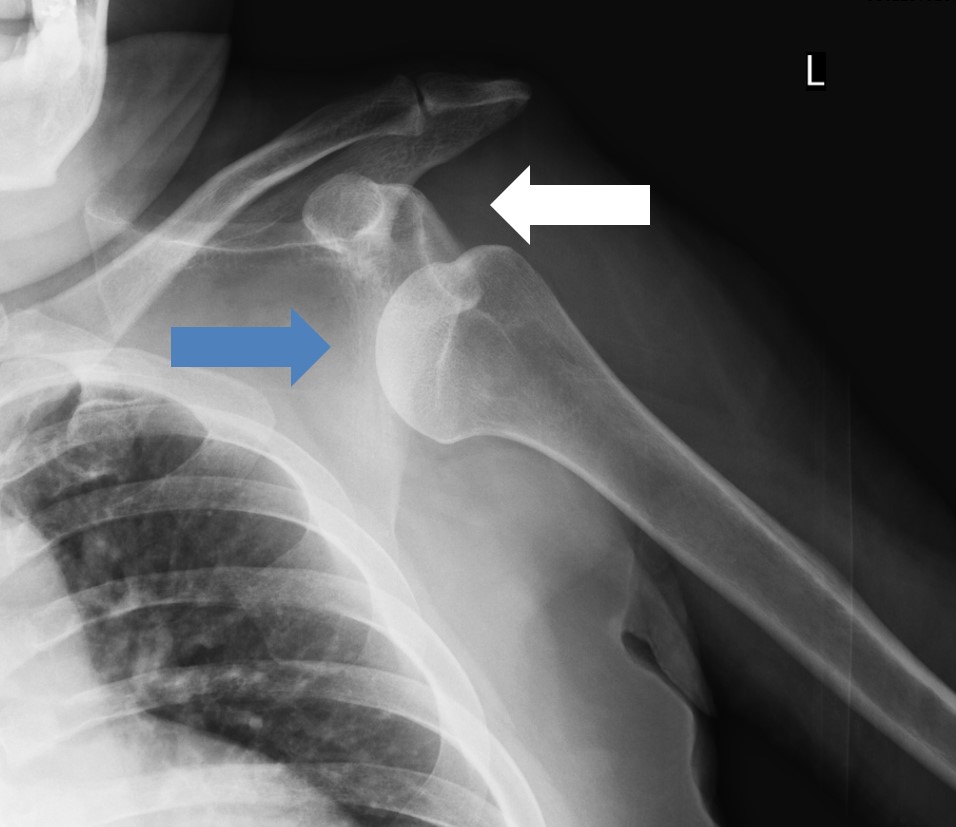

在肩關節上舉狀態(雙手舉起的狀態)下從後方施加外力、從後方拽手、摔倒時手撐在後方等情況下,處於不穩定狀態的肱骨頭從關節面滑脫導致脫位。脫位的類型多為肱骨頭移動到身體前面的前方脫位型(照片1)。

照片1 左肩關節脫位(白色箭頭是骨頭本來的位置)